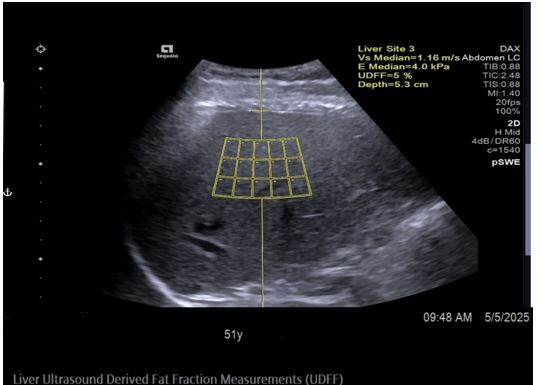

Ultrasound-Derived Fat Fraction (UDFF) for Monitoring Liver Steatosis in MASLD: A Case Report

Kiran Mukhtar, Shafaath Husain Syed Mohammed, Muhammad Raza Qureshi, Faiz Ul Amin

A Case Report | 15 Oct 2025